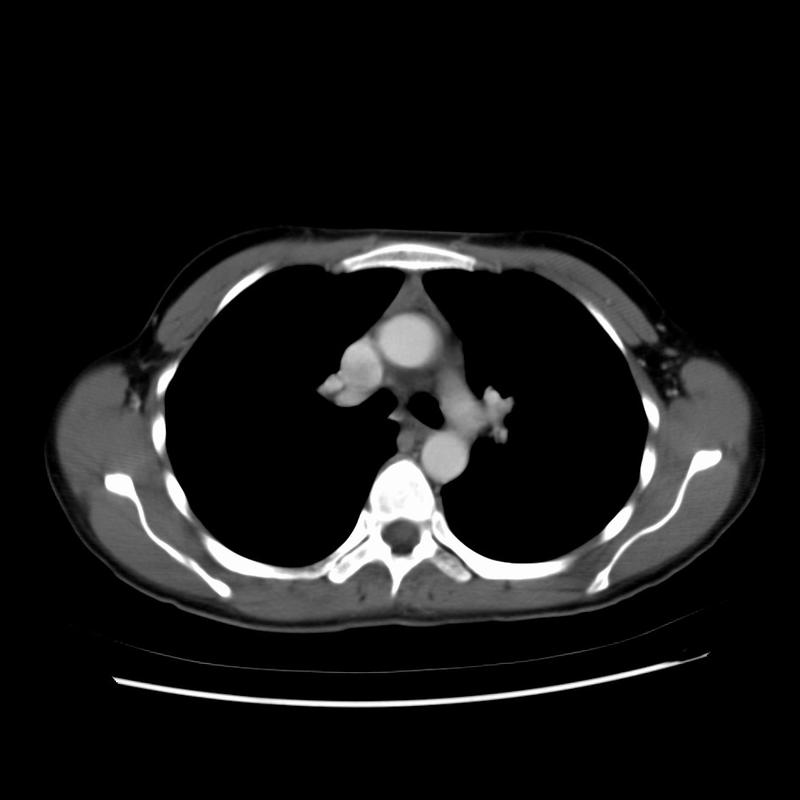

Normal Thymus